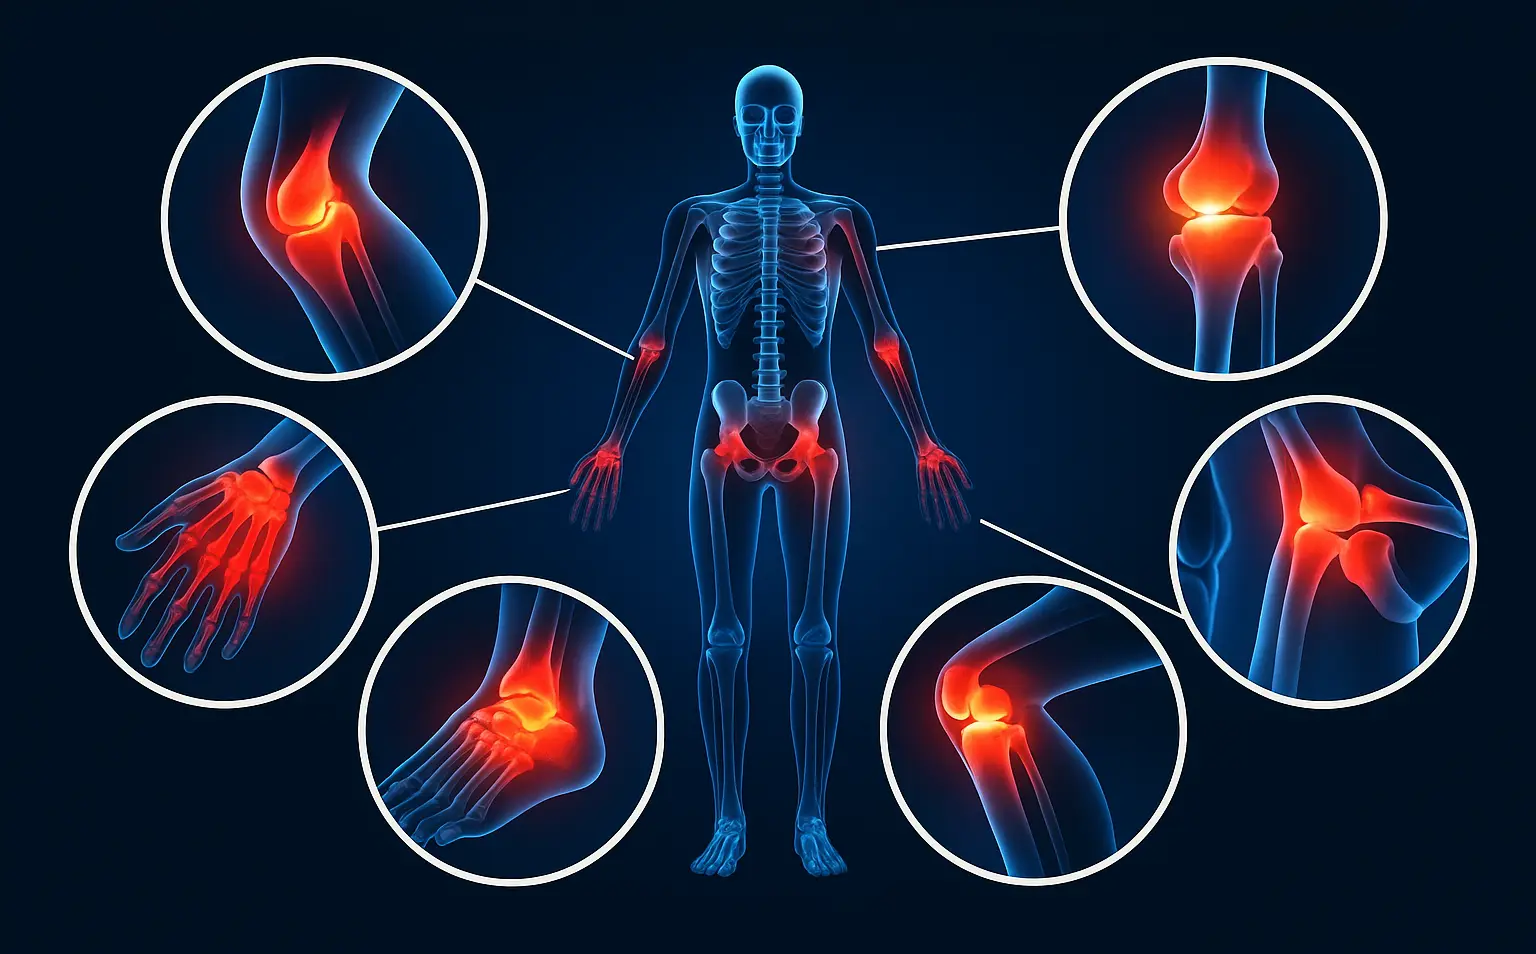

Локализация ревматоидного артрита

При ревматоидном артрите преимущественно поражаются суставы, которые расположены симметрично. Болезнь начинается с мелких суставов кистей и стоп, постепенно воспаление распространяется на более крупные сочленения. Места поражения зависят от стадии болезни, индивидуальных особенностей организма.

Типичные области поражения:

- Суставы кистей. Чаще всего воспаляются пястно-фаланговые и проксимальные межфаланговые суставы. Появляется боль при сжатии кулака, скованность по утрам, затем появляются деформации пальцев.

- Запястные суставы. Развивается боль при движении кистей, снижается сила хвата, возможны подвывихи.

- Суставы стоп. Поражаются плюснефаланговые суставы, боль усиливается при ходьбе, возможны деформации пальцев, нарушение походки.

- Локтевые, плечевые суставы. Воспаление вызывает боль, затруднение движений, иногда возникают ревматоидные узелки.

- Коленные суставы. Часто вовлекаются при длительном течении болезни; появляется отек, ограничение сгибания и разгибания.

- Шейный отдел. При вовлечении суставов шеи возникают боли в затылке, чувство скованности, головокружение.

Хотя заболевание начинается с суставов, запущенное воспаление может прогрессировать, затрагивая соседние или отдаленные органы. Встречаются внесуставные проявления ревматоидного артрита, когда страдают легкие (одышка, кашель), сердце (перикардит, нарушения ритма), сосуды, глаза (сухость, раздражение), кожа.